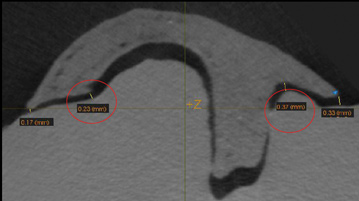

Fig 3. A 3D printed scaffold was designed using CAD software to fit a peri-osseous defect in a human patient. The scaffold consisted of a region with channels designed to support oriented PDL tissue formation and a region for the regeneration of osseous tissue. Fig 3: baseline;

Fig 4: defect model; Fig 5 through Fig 7: internal, tilted, and side views of scaffold, respectively; Fig 8 through Fig 10: coronal, middle, and apical

angles, respectively; Fig 11: cross-section diagram; Fig 12: labial scan image. (Images reprinted with permission from Rasperini G, Pilipchuk SP, Flanagan CL, et al. J Dent Res. 2015;94[9 suppl]:153S-157S.)

Synthetic polymers such as polycaprolactone (PCL) and poly-L-lactic acid (PLA) can be combined with natural polymers such as hydroxyapatite and β-tricalcium phosphate to allow the formation of biphasic constructs with tailored mechanical properties and rates of degradation. Recently, a first-in-human case report of a custom-designed, 3D-printed PCL scaffold for the treatment of a large periodontal defect was reported in combination with PDGF administration (Figure 3 through Figure 20).23 The scaffold was fabricated using selective laser sintering, which allowed for material powder to be fused together to form a structure based on a CAD file of the scaffold that was designed from CBCT scans of the patient defect. This novel approach offers a promising future application of 3D printing for customized scaffold designs that can be tailored to meet patient-specific needs based on defect site and location, with the added ability to deliver growth factors.